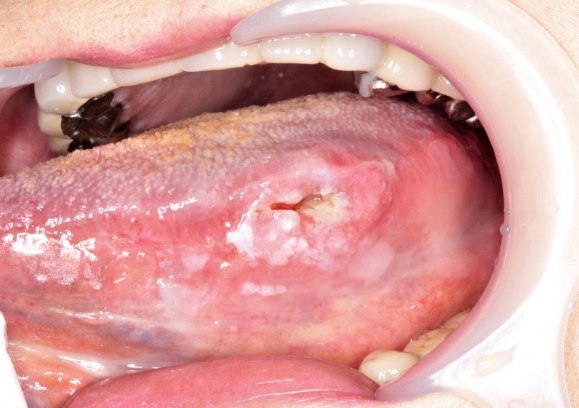

口腔がん

お口の中にも癌ができることをご存知ですか